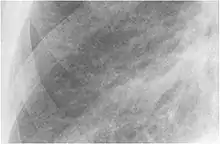

The abnormal chest x-ray and its interpretation remain the most important factors in establishing the presence of pulmonary fibrosis.[11] The findings usually appear as small, irregular parenchymal opacities, primarily in the lung bases. Using the ILO Classification system, "s", "t", and/or "u" opacities predominate. CT or high-resolution CT (HRCT) are more sensitive than plain radiography at detecting pulmonary fibrosis (as well as any underlying pleural changes). More than 50% of people affected with asbestosis develop plaques in the parietal pleura, the space between the chest wall and lungs. Once apparent, the radiographic findings in asbestosis may slowly progress or remain static, even in the absence of further asbestos exposure.[25] Rapid progression suggests an alternative diagnosis.